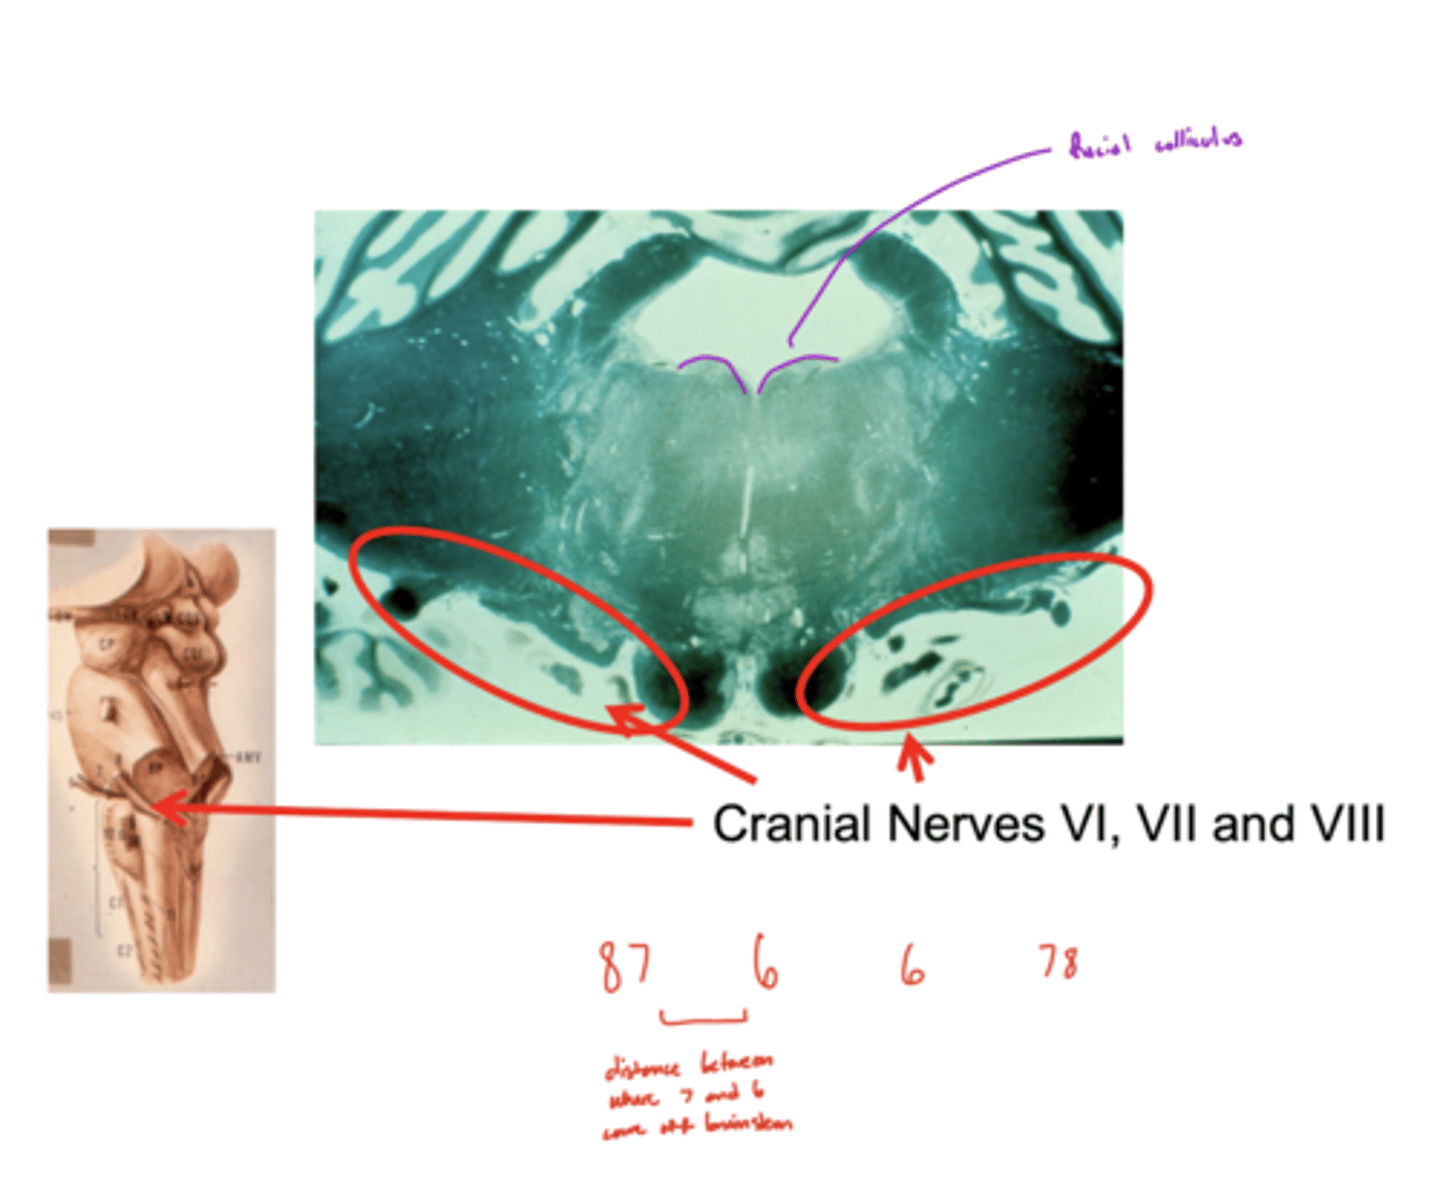

What nuclei are at the pontomedullary junction?

1. SVE of CN VI

2. SVE of CN VII (facial)

What are the facial colliculi?

bumps (hills) coming out from dorsal pontomedullary junction into the 4th ventricle -- CN VII SVE fibers create this space when they wrap around the abducens nucleus

Where do CN VI, VII, VIII exit the pons?

pontomedullary junction

What is the spacing of CN VI, VII, and VIII exiting the pontomedullary junction?

8 & 7 -- lateral and closer together

6 -- medial and far away

image -- look at red font